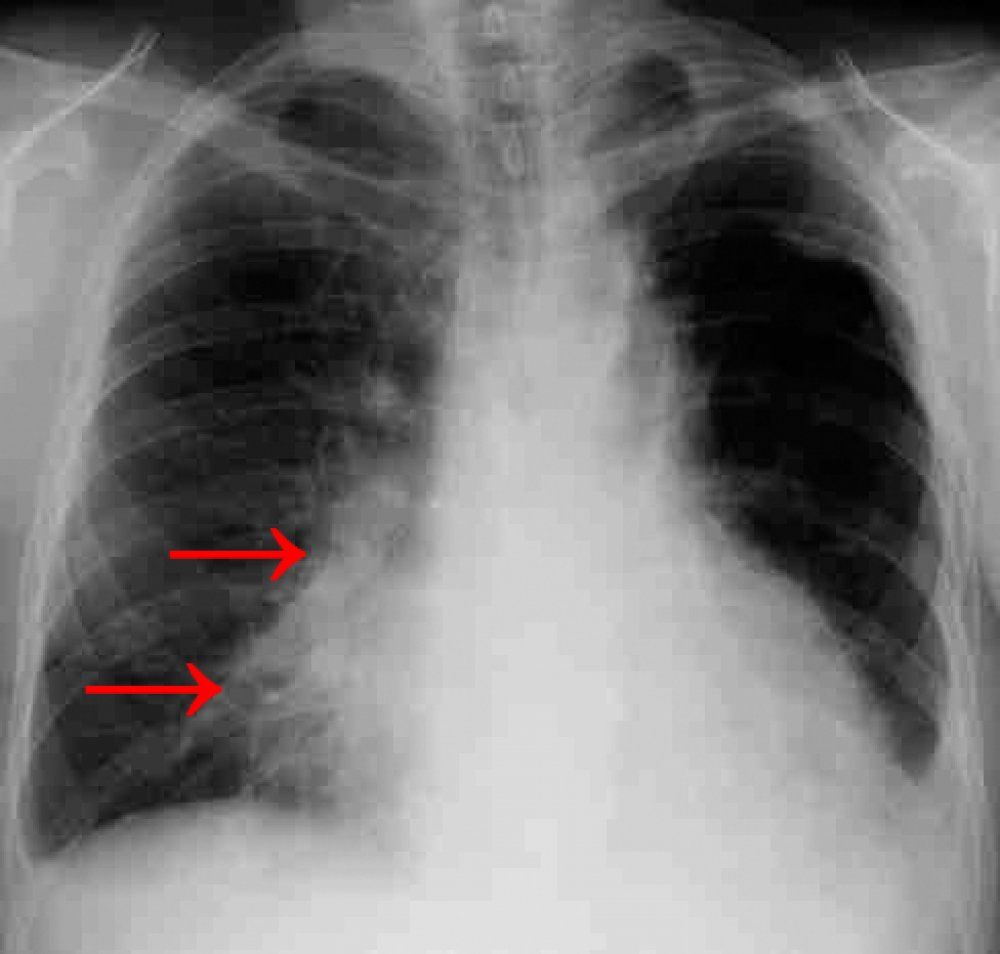

При наличии такого заболевания, как пневмония, на снимках видны множественные уплотнения в нижних сегментах лёгкого.

Первый признак пневмонии на рентгеновском снимке – появление очагов затемнения с неровными контурами в разных частях легкого, которые могут иметь разный размер, от 3-4-х до 12 мм.

Тени различают по внешнему виду (круглые, овальные кольцевидные) и интенсивности окраски – чем темнее пятно, тем сильнее выражен патологический процесс.

- Очаговая форма. На рентгене отображаются небольшие (1-1,5 см) тени со слабой или умеренной интенсивностью окраски, неоднородной структурой и нечеткими границами. Очаги поражения могут быть единичными или множественными, а в некоторых случаях они сливаются в одно большое пятно. Корни легких расширены, причем нарушения нормального рисунка органа могут сохраняться в течение нескольких дней после выздоровления.

- Крупозная пневмония. Наблюдаются изменения нормального легочного рисунка, жидкость в полости плевры, признаки инфильтрации одной из долей легкого, расширение корней. По мере развития воспалительного процесса выраженность изменений и интенсивность окраски затемнений усиливается.

Конечный результат картинки получается неоднородным. При здоровых легких структура как раз отличается однородностью. Если присутствует пневмония, на рентгеновских снимках затемненные участки уплотнений указывают на очаги воспаления. Высветленные участки – ткани воздушные. Диагноз пневмонии по снимку ставится в том случае, когда имеются:

- одиночные или множественные пятна;

- сегментарные уплотнения;

- светлые и затемненные конкретные участки;

- измененные корни легких.

Пневмония на снимке флюорографии

В нижней части легких на каждом конкретном снимке в таких случаях видны воспалительные участки. Определяются очаги воспаления размером более 5 мм, которые расположены на чистых участках легких. Но при проведении последующей рентгенодиагностики эти очаги подтверждаются не всегда.

При флюорографии рисунок не всегда четкий. Подозрение на развитие пневмонии на снимке возникает из-за видимых очагов инфильтрации, а также пятен на фоне тени сердца. Даже 1 отклонение требует продолжения диагностики.

О развитии пневмонии на снимке флюорографии будет говорить также наличие множественных инфильтратов в нижних долях легких.